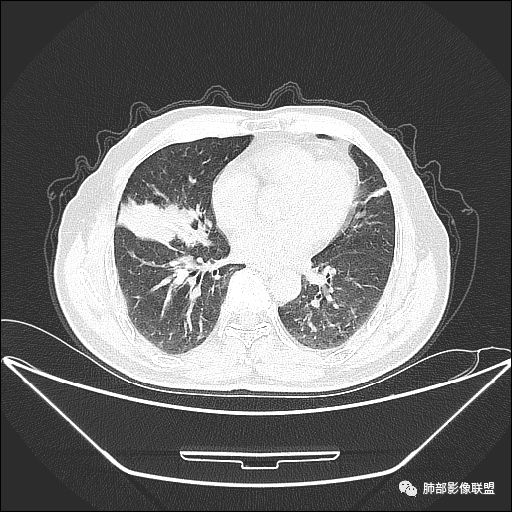

住院4天后行胸部增强CT

静脉期

老年男性,因“咳嗽咳痰1月余。”入院。病程中咳嗽咳痰,咳黄白痰,间断咯少许鲜红色痰血。PPD阳性。胸CT:右肺中叶外侧段支气管管腔阻塞,大片实性病变,病灶边缘光滑,部分边缘膨隆,可见分叶,肺门及纵隔可见肿大淋巴结,并可见钙化。增强可见病灶明显强化,而且延迟强化明显,病灶内多发低密度区,内见血管影,血管变细、部分血管破坏。考虑恶性病变可能性大,鉴别慢性肉芽肿性病变。

胸CT:跨叶大肿块,主体在中叶,右中叶外侧段支气管阻塞,病灶部分边缘膨隆,可见分叶,部分边缘平直,肺门及纵隔可见肿大淋巴结。增强病灶不均匀强化,延迟强化明显,病灶内多发低密度区,内见血管飘浮,部分血管变细、模糊。考虑:恶性病变可能性大,大细胞?淋巴瘤?鉴别慢性肉芽肿性病变。

右肺中叶软组织肿块,外围向内生长,叶间胸膜向前内移位,肿块近肺门侧跨叶,中叶外侧段支气管截断,密度不均匀,双侧肺门及隆突下见肿大淋巴结,增强后呈中度不均质强化,肺动脉供血,多发坏死区,边界尚清,坏死区域内见结构,结合病史考虑恶性,鉴别诊断1结核,爬行征是沿支气管树分布,外宽,内窄,周围有卫星灶,内气管狭窄后扩张,此例沿叶间胸膜长轴分布,气管有截断,不典型。2炎性肉芽肿,符合的地方下方层面增强后延迟性轻度环形强化,不符临床无发热等急性感染病史,实验室指标不符,病灶周围渗出及慢性炎性改变有,不明显。

吴婧老师和南边老师都对该病例进行了深入分析。从支气管管壁的增厚,支气管狭窄后扩张,支气管粘液栓,病灶形态,到病灶不均匀强化及坏死彻底,到周边病灶及肺组织空气的潴留,加之纵隔内淋巴结肿大伴钙化等等,都支持慢性炎性病灶,尤其是结核。

墨西哥仙人掌征---结核        影像上结核灶,粗大的均匀枝干,推测是支气管囊状扩张引起的,在非支气管区,形成圆形坏死囊群;如果这些坏死比较稀薄,又遇到扩张支气管,就会形成粗大的“墨西哥仙人掌”。结核引起的支气管近端炎症纤维化,可以造成支气管阻塞,从而将干酪样坏死物封堵在管腔内。仙人掌主干内部应该是干酪为主,稀薄的,具有流动性,时间久了会出现钙化。